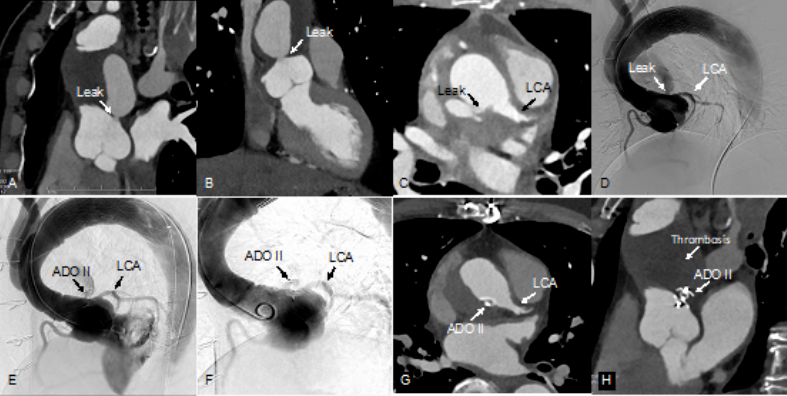

患者,男,61岁,升主动脉替换+全弓支架象鼻术后,窦管交界处吻合口漏

图A,B:主动脉CT三维重建从不同角度展示吻合口漏;

图C,D:主动脉CT和DSA显示吻合口漏与左冠状动脉关系和距离;

图E:术中封堵器释放前,复查造影,显示LCA开口显影良好;

图F:释放封堵器后复查造影,证实冠状动脉显影良好,不受封堵器伞盘影响;

图G:术后1个月复查主动脉CTA,提示封堵器位置良好,LCA显影良好;

图H:吻合口漏完全封闭,假性动脉瘤完全血栓化。